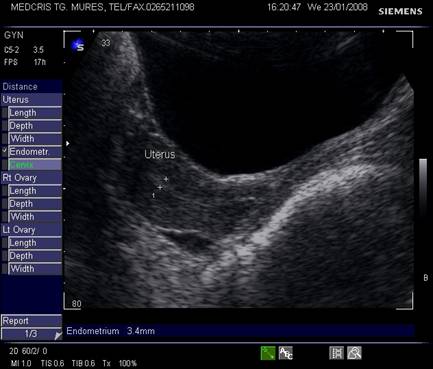

Dimensiunile uterului la o pacienta nulipara matura, masurate transvaginal sunt de 7,3 cm x 4,0 cm x 3,2 cm. In general dimensiunile cresc cu paritatea si scad dupa menopauza.

Raportul intre corp si col este aproximativ de 1,6 in ceea ce priveste lungimea.[5,6]

Endometrul - grosimea sa este apreciata in sectiune longitudinala. Masurarea se va face de la interfata miometru - endometru la interfata identica, opusa, de pe peretele celalat uterin. Maxim acceptat normal este de 1,5 cm in perioada de premenopauza.[5] Postmenopauza in mod normal nu depaseste 5 mm, de obicei este atrofic si apare ca o imagine ecogena lineara. Daca apare o colectie anecogena postmenopauzala intrauterina, prin atrofie cervicala, aceasta colectie nu trebuie sa fie masurata la calculul grosimii endometriale.[2,6]